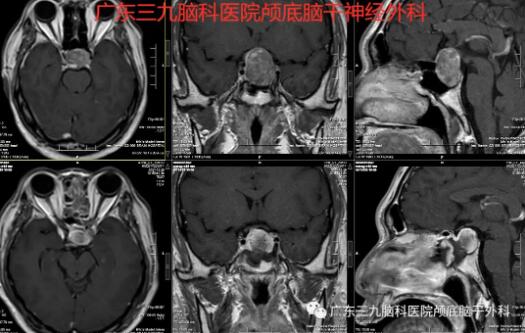

听说脑子里长了瘤子,王先生顾虑重重,担心要开颅切瘤。张良医生告诉他,可以从鼻孔里进去,将瘤子摘除掉。完善术前检查后,12月21日,由张良主刀行神经内镜经鼻蝶鞍区占位性病变切除,手术经过鼻孔,通过打开蝶窦进入垂体窝,借助神经内镜的帮助,在较小的手术空间下将垂体瘤从鼻子里摘了出来。术后病理示: (鞍区)垂体腺瘤/垂体神经内分泌肿瘤。

术前术后MR